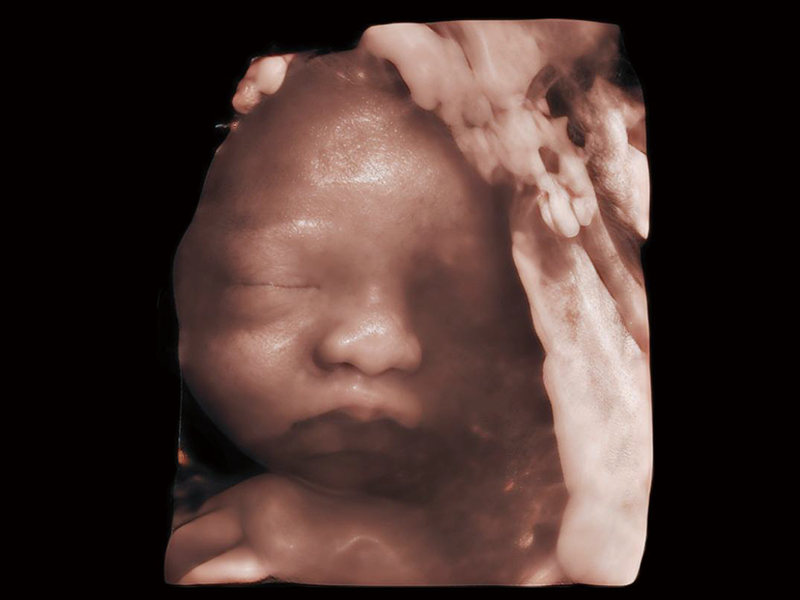

作為開立醫(yī)療全新打造的超高端旗艦超聲產(chǎn)品,從探頭抬起喚醒開啟掃查到多維探頭發(fā)射接收,通過先進(jìn)的場(chǎng)成像發(fā)射、自適應(yīng)聚合重建等技術(shù),基于RF Data原始射頻數(shù)據(jù)在圖像生成、高端功能等方面實(shí)現(xiàn)突破,為婦產(chǎn)科、兒科提供全方位臨床解決方案。

夢(mèng)溪?P80以“關(guān)愛女性”為基石,提供全方位的解決方案,量身定制以滿足女性的健康需求,涵蓋婦科、生殖健康檢查、產(chǎn)前篩查及產(chǎn)后康復(fù)等領(lǐng)域。